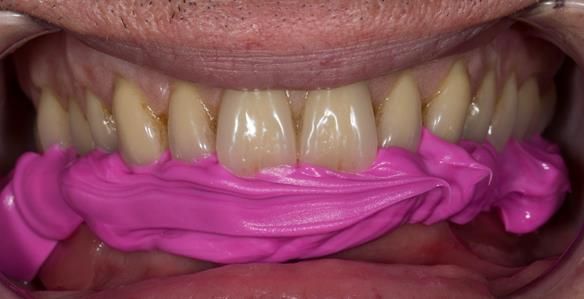

This newsletter describes in step by step detail the transition from acrylic based immediate dentures to metal based definitive dentures.

The clinical situation and treatment process is shown in detail below with photographs.